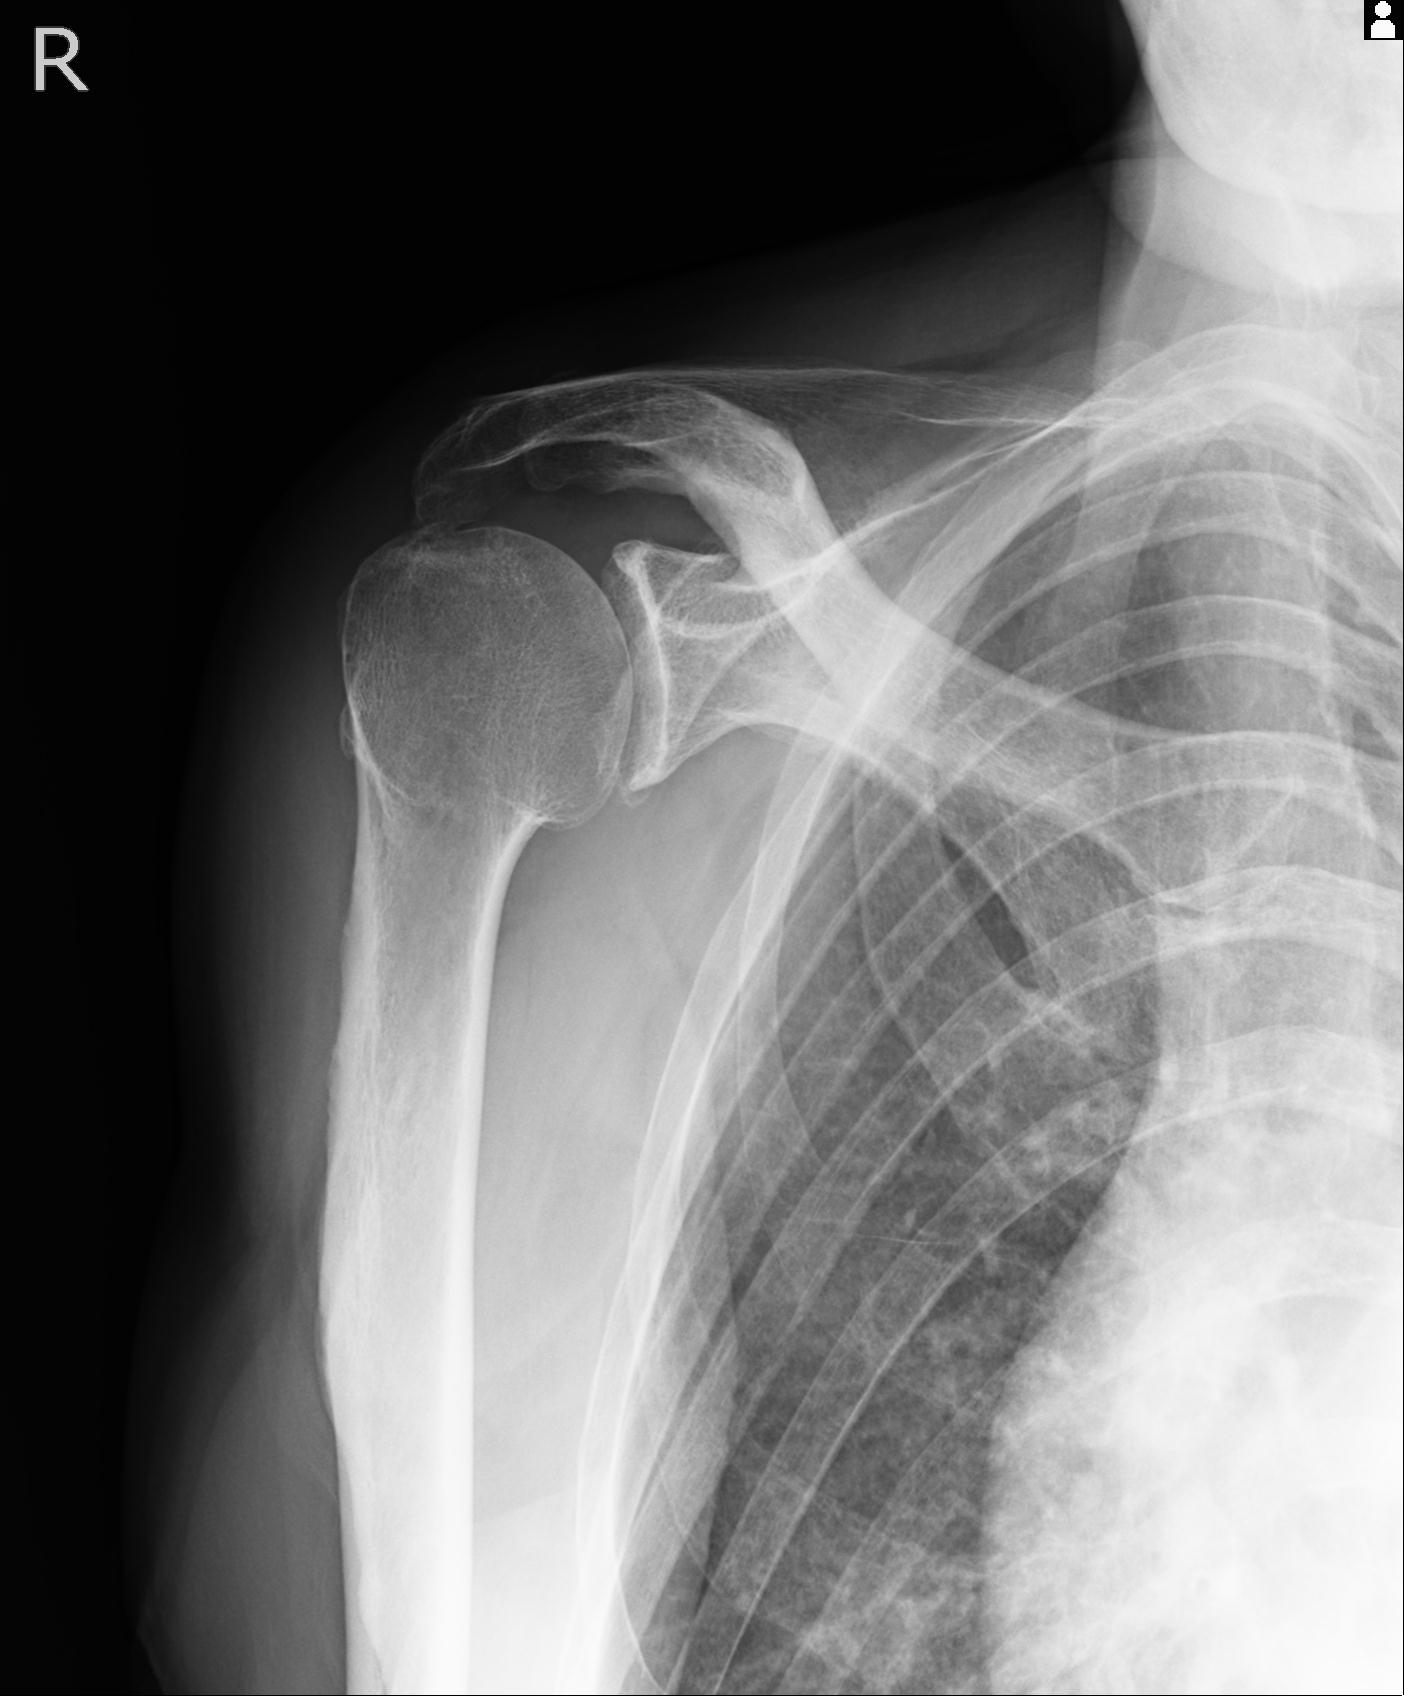

110214 12/20 肩 2R 12/21 肩 4R 72歳女性 左上腕外科頚プレート